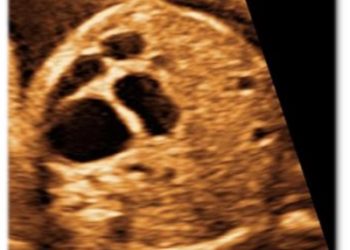

Per il mese di Dicembre SIEOG Giovani presenta il Webinar sullo screening delle cardiopatie congenite nel primo trimestre. La registrazione...